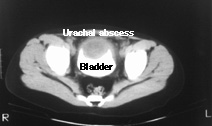

The scan shows contrast within the bladder (bright white area). However, there is a filling defect (gray area) on the anterior dome of the bladder. This is a urachal abscess.